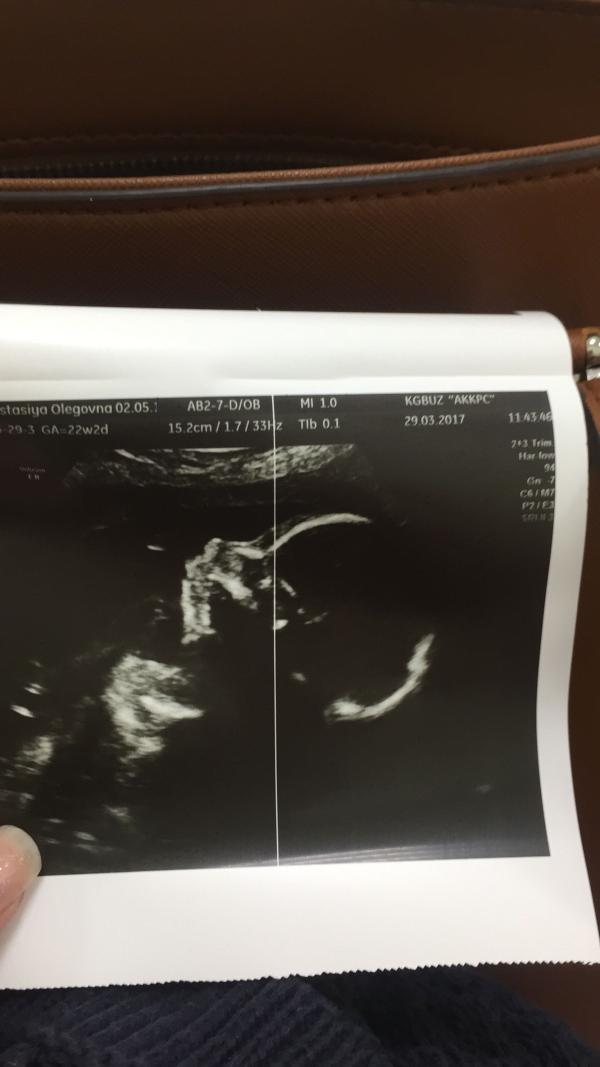

Видимо правду говорят, что беременность не проходит одинаково😇

В первую беременность единственным признаком моего положения был растущий живот🤰🏻Не было тошноты, усталости, сонливости, причуд с потребностью в еде, ни каких капризов! Я радовалась каждому мгновению и если честно не хотела расставаться с этим положением🤰🏻

Сейчас вторая беременность, всего 7 недель (и то акушерских)🤔

Вторая Беременность✨Часть 2